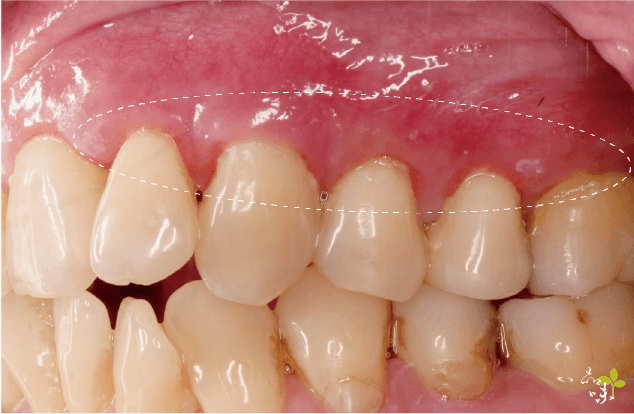

通常做完的病人牙齒敏感的狀況會改善很多,美觀上有改善,牙齒不會看起來這麼長。

治療時,醫生會用特殊的針,在患部牙齦上刺一個小洞,接著使用專利的器械,透過這個針孔從內部翻瓣,再填入再生膜。一般來說,可以恢復原有牙齦高度的 80-90%。